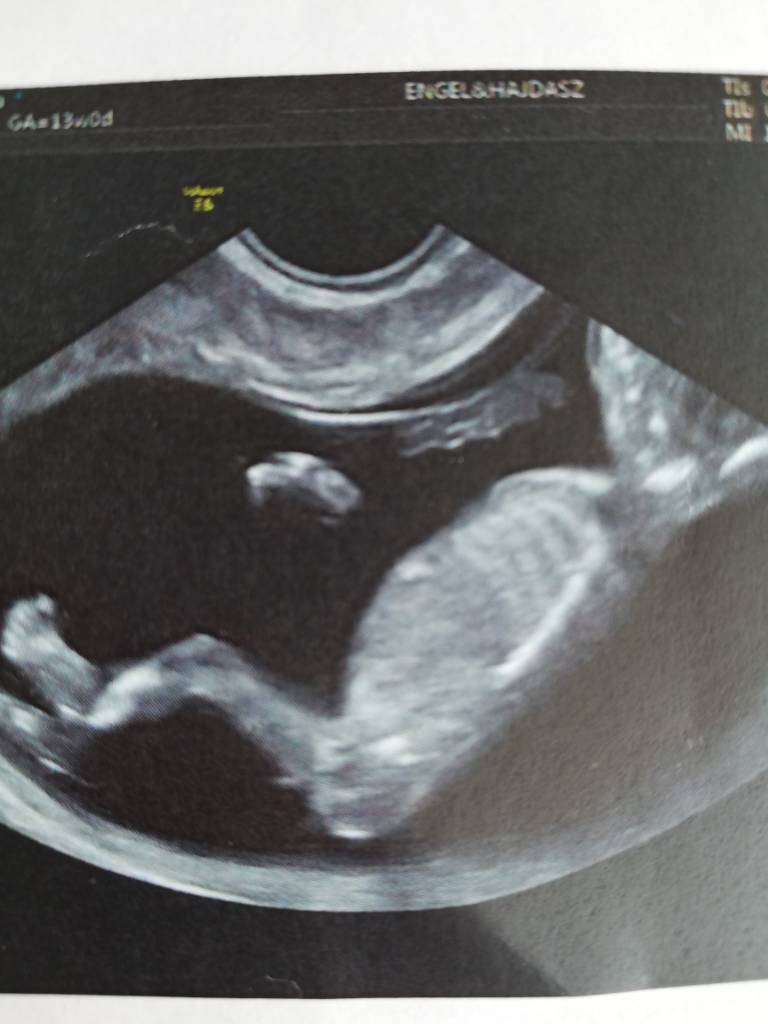

Cudne zdjęciaJa wczoraj byłam na prenatalnych ale po wizycie żeby uczcić poszłam na zakupy a wieoeczorem szybko padlam więc dzisiaj pisze dopieroDzidziuś ma już 6,61 cm tydzień ciąży identyczny jak z usg 13+0. Termin na 02.04. Wszystkie wymiary idealne, pięknie fikal dzidziuś

Wstępnie dr obstawia dziewczynkę ale jeszcze mamy się nie nastawiac. Trochę szok dla mnie bo byłam pewna że będzie drugi chłopczyk. Zobacz załącznik 901859Zobacz załącznik 901860Zobacz załącznik 901861Zobacz załącznik 901863